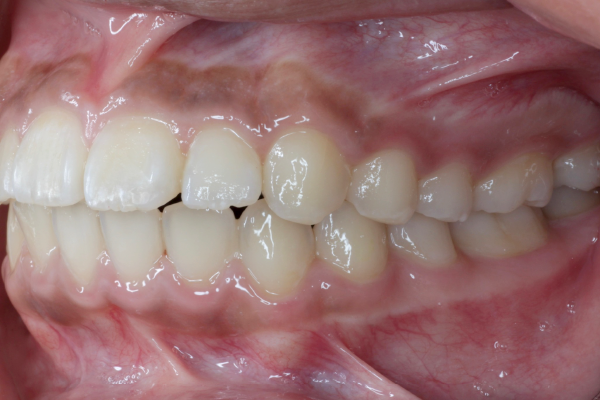

抜歯を避けた10代女性のワイヤー矯正の症例

患者様は10代の女性で、以前から歯並びのガタつきが気になり、「将来を考えて今のうちにきれいにしておきたい」という思いから、札幌駅前で矯正治療をご相談に来院されました。

精密検査では、前歯部を中心とした叢生(歯の重なり)が確認され、現在だけでなく将来的な口腔環境も考慮した治療方針について詳しくご説明した上で、矯正治療を開始することとなりました。

患者様は10代の女性で、前歯を中心とした歯並びのガタつき(叢生)を気にされて来院されました。できるだけ抜歯をせずに矯正治療を行いたいというご希望があり、精密検査を実施しました。

検査の結果、歯列全体のスペースバランスを調整することで、抜歯を行わずに歯並びの改善が可能と判断しました。歯の移動量やコントロール性を考慮し、今回はワイヤー矯正を用いた治療計画をご提案し、患者様にも十分ご理解いただいた上で治療を開始しました。